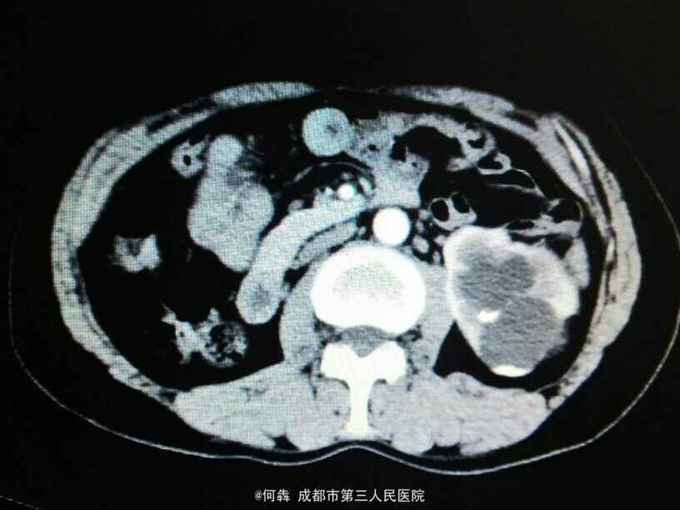

左肾区轻叩痛。尿常规:白细胞72个/ul。CT见图片。左侧GFR42.27,右侧GFR14.46。

左肾盂输尿管交界处结石 左肾重度积水,左肾结石,右肾萎缩,尿路感染。